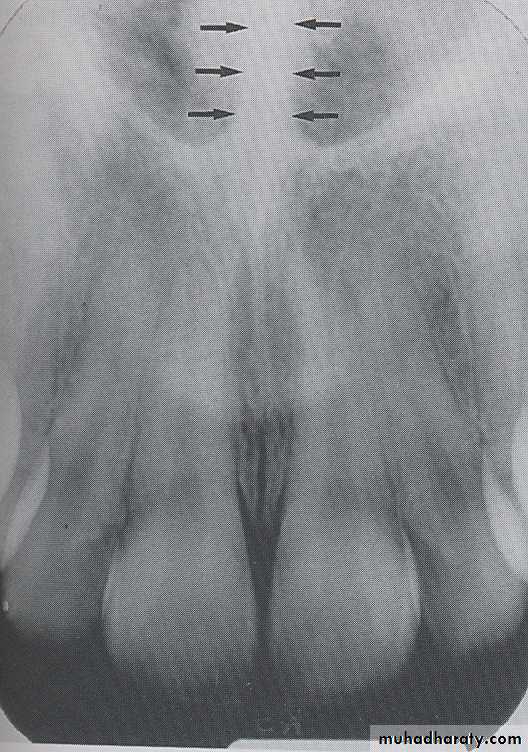

INCISIVE FORAMEN: The incisive foramen is an opening in the bone that is located at the midline of the anterior portion of hard palate. Radiographically the incisive foramen appears as a small ovoid or round radiolucent area located between root of maxillary central incisor.

Superior Foramina of Incisive Canal

The superior foramina of the incisive canal are two tiny openings or holes in bone that are located on the floor of the nasal cavity. The superior foramina are the openings of two small canals that extend downward and medially from the floor of the nasal cavity. These two small canals join together to form the incisive canal and share a common exit, the incisive foramen.Appearance. On a maxillary periapical image, the superior foramina appear as two small, round radiolucencies located superior to the apices of the maxillary central incisors

MEDIAN PALATEL SUTURE: The median palatal suture is the immovable joint between two palatine process of maxilla. Radiographically the suture appears as thin radiolucent line between the central incisor, the median palatal suture bounded in both side by dense cortical bone that appear radiopaque.